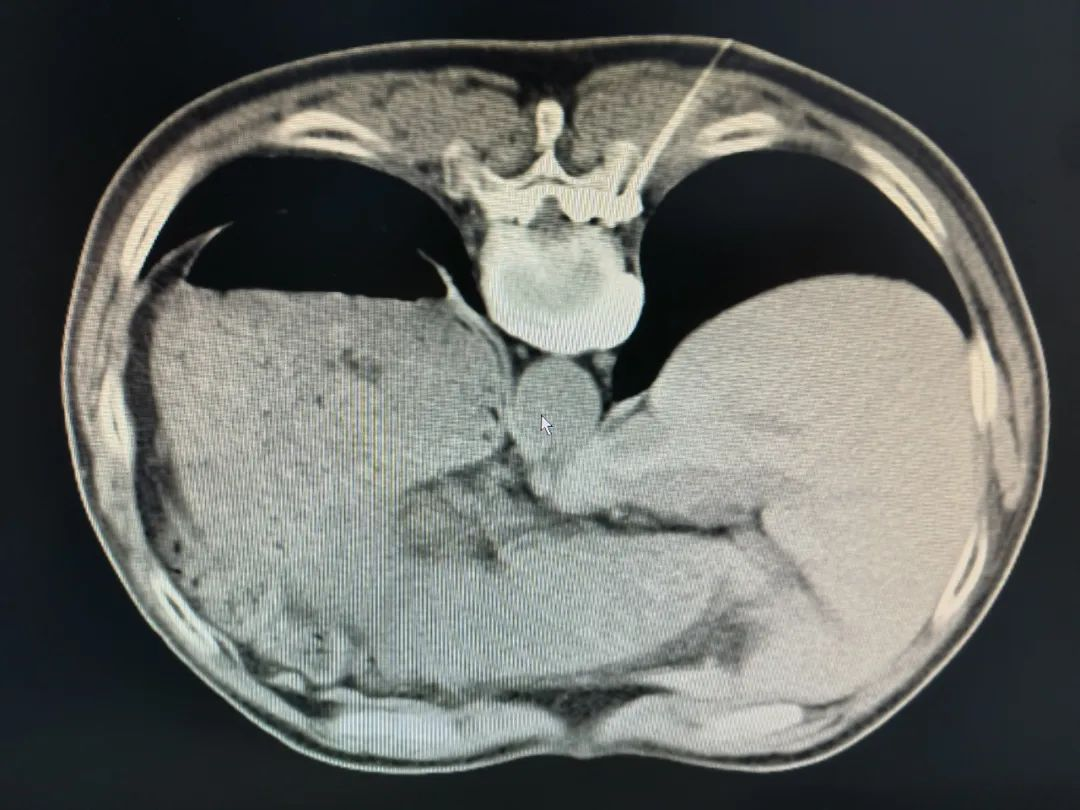

该患者属于“带状疱疹性神经痛(右T9、10)”口服镇痛效果差,严重影响了患者的生活及睡眠,同时给患者及家属都带来了极大的生活困扰。入院后,学科带头人王志鹏主任马上组织疼痛组组长彭思进及团队进行病情讨论,最终考虑予以微创背根神经节脉冲射频术。在做好充分的术前准备后,彭思进组长带领团队于局部麻醉及CT引导下,利用穿刺手段精准地将穿刺针置入相应右侧T9、10背根神经节,予以刺激可以完全覆盖疼痛区域,予以长时程、高电压脉冲射频治疗,手术顺利完成。

术中图片

CT引导下精准穿刺